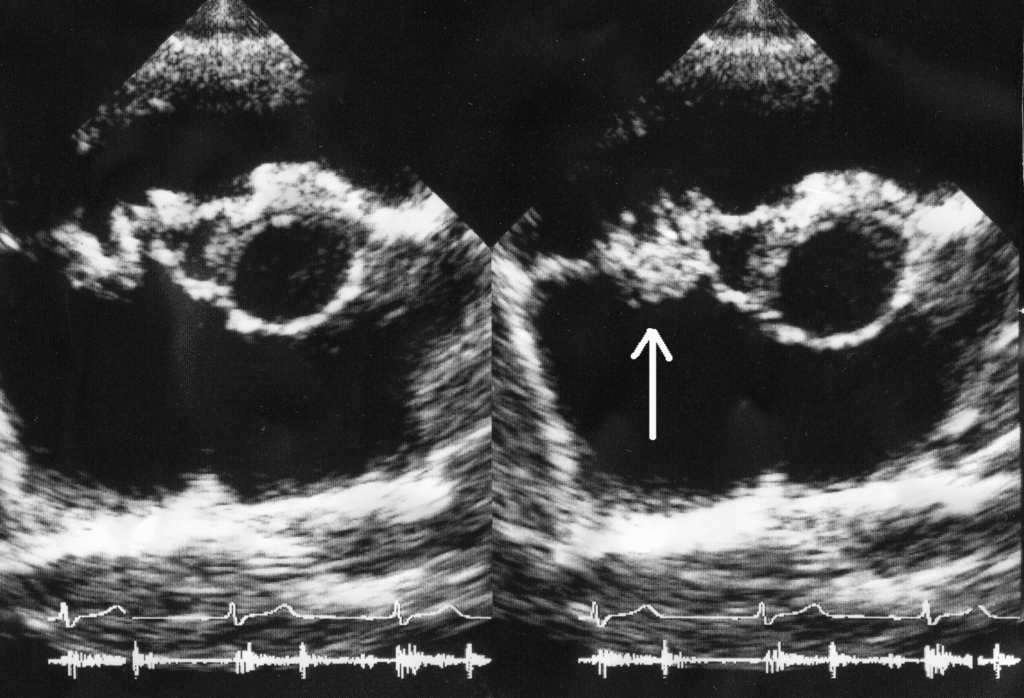

Endocarditis ultrasound

Vegetation on tricuspid valve by echocardiography. Arrow denotes the vegetation.